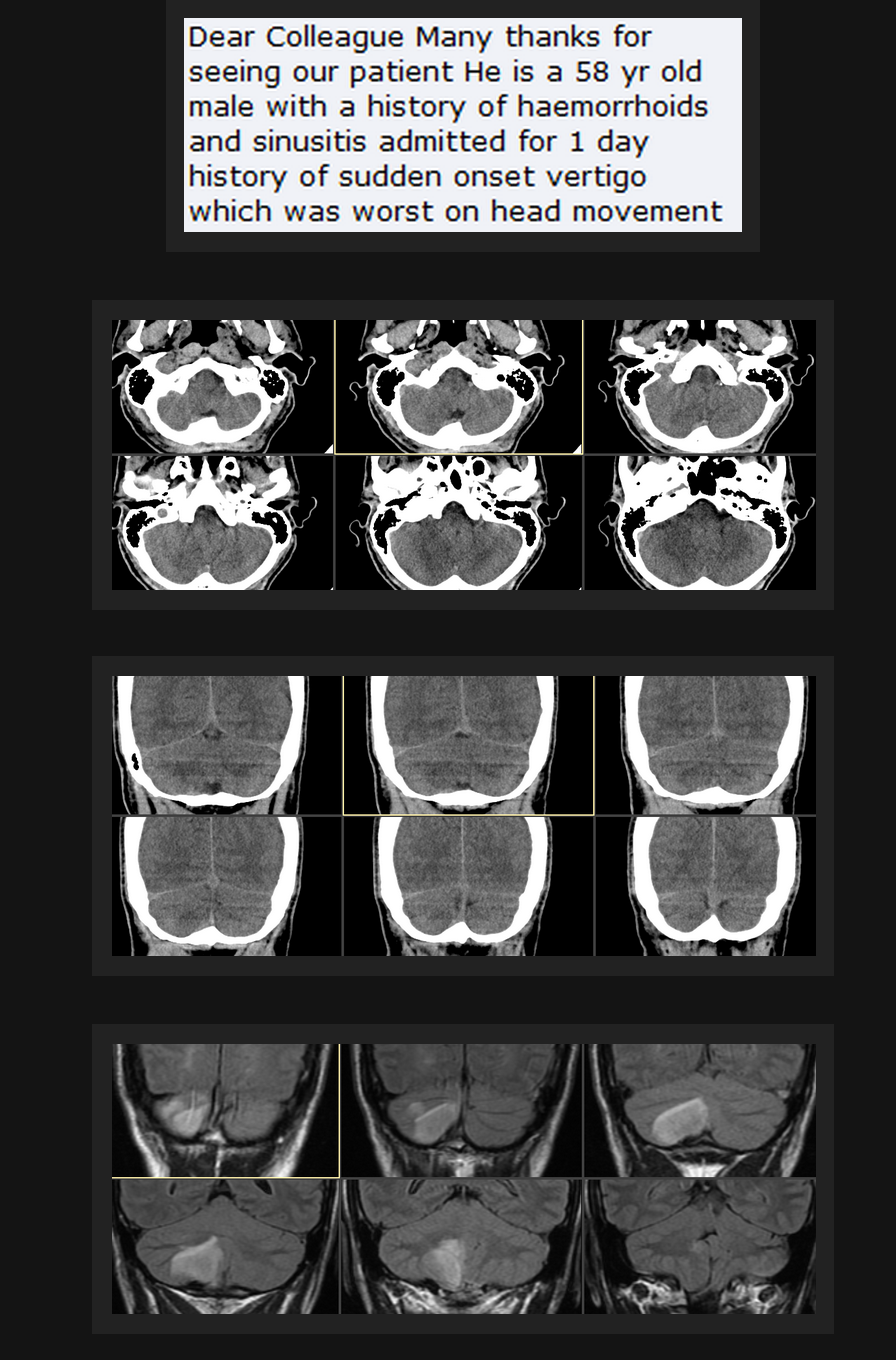

(above 2 images screenshots from AJNR Case of the Week menu pages)